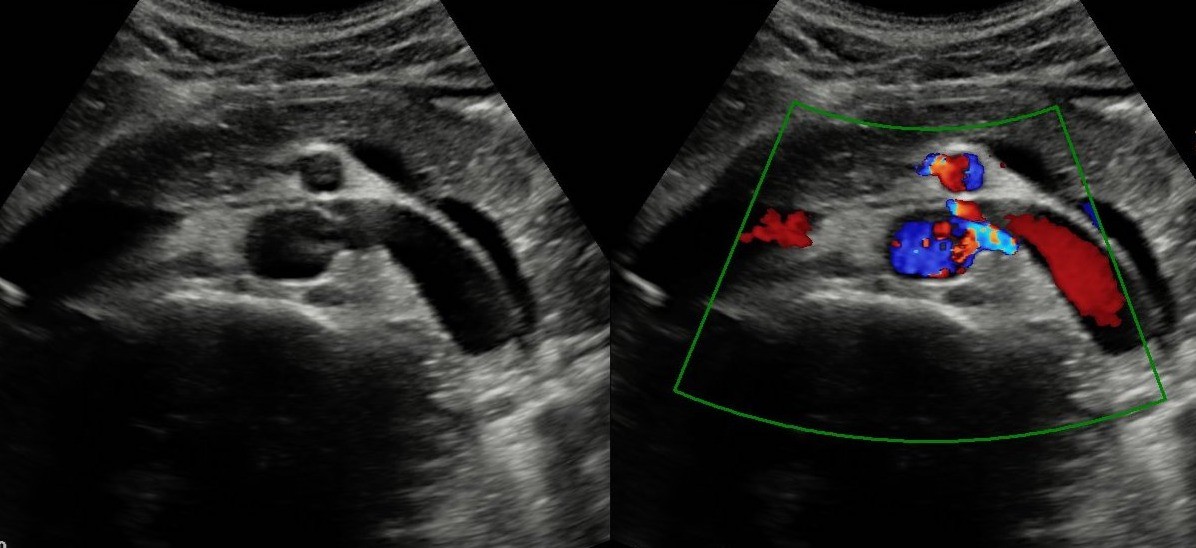

Ecografía clínica: La ecografía abdominal realizada en consulta mostró riñones normotróficos, sin litiasis ni hidronefrosis. La vía urinaria y el parénquima renal eran normales. Al evaluar grandes vasos abdominales se observó dilatación proximal de la vena renal izquierda y estrechamiento marcado en el ángulo formado entre la arteria mesentérica superior y la aorta, hallazgo sugestivo de síndrome de cascanueces. No se identificaron alteraciones anexiales ni signos de diverticulitis.

Dolor abdominal secundario a congestión venosa renal por síndrome de Cascanueces. Se descartaron cólico nefrítico, pielonefritis, patología diverticular, enfermedad inflamatoria intestinal y procesos ginecológicos agudos.